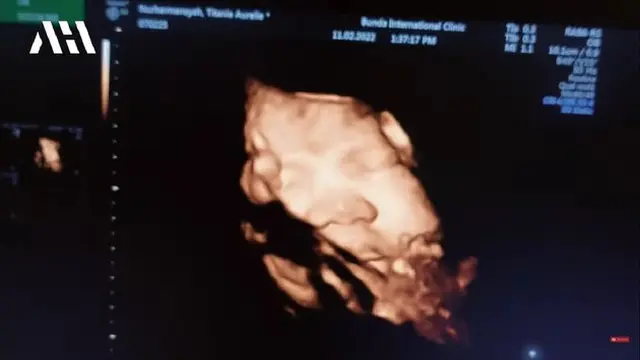

Saat melakukan cek kandungan, salah satu tindakan dokter pada Aurel adalah USG. Hal tersebut dilakukan untuk melihat perkembangan janin dalam perut istri Atta Halilintar ini.

Wajah dari calon anak Aurel pun terlihat jelas, disebut hidungnya mirip dengan Atta. "Ya Allah, itu hidung. Sayang itu kamu banget," ujar Aurel Hermansyah.

Melihat calon anaknya dalam keadaan sehat, Aurel pun mengaku gemas. "Aduh.. aduh... aduh, ini udah mau keluar," kata seorang perempuan yang tak terlihat wajahnya. "Gemes banget," timpal Aurel.